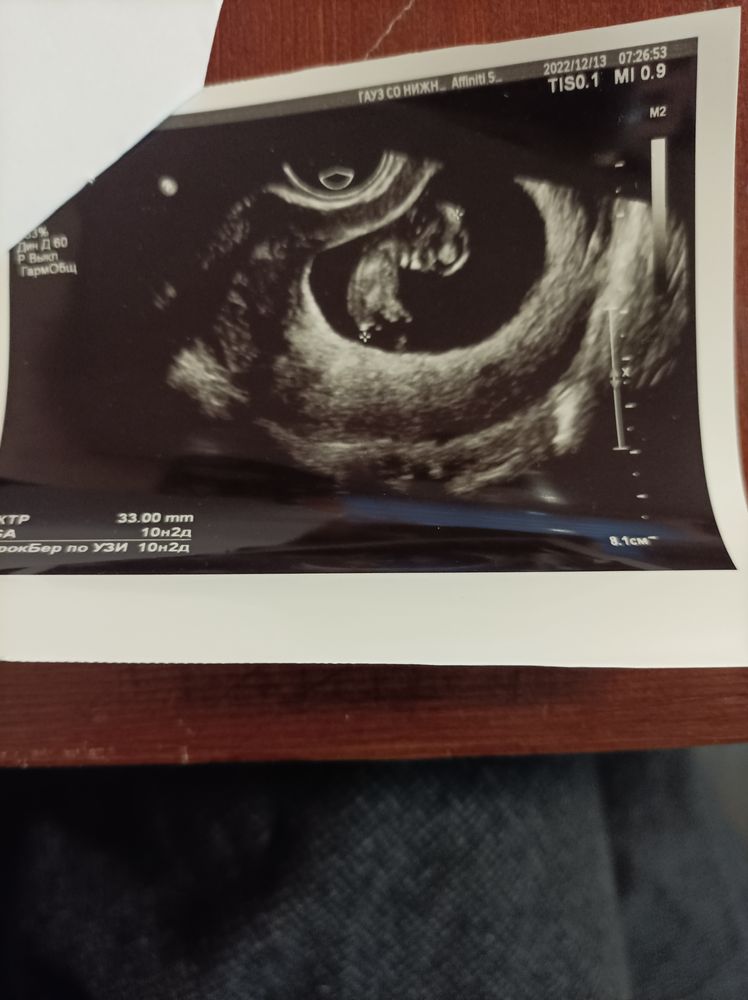

Малышарик все таки один, второго не нашли.... Я сначала конечно расстроилась немного.... Но потом показали, как он барахтается, ручками и ножками дрыгает.... ❤❤❤😍😍😍😍 прям не могу.... Мать конечно растаяла, лишь бы здоровенький.... Ну или это девчулька может.... ЧСС наметили аж 175уд в минуту....

Срок поставили на неделю больше, бутузика будем ждать или бутузку 😂❤😜 еще и скрининга не было, а мы уже вместо 9+4дня выросли на 10+2дня😊😊😊😊

Из грустного пока плацента перекрывает зев и по задней стенке.... Ползти будет долго видимо.... Лишь бы уползла.... 🙏🙏🙏🙏🙏

Ну и фото: